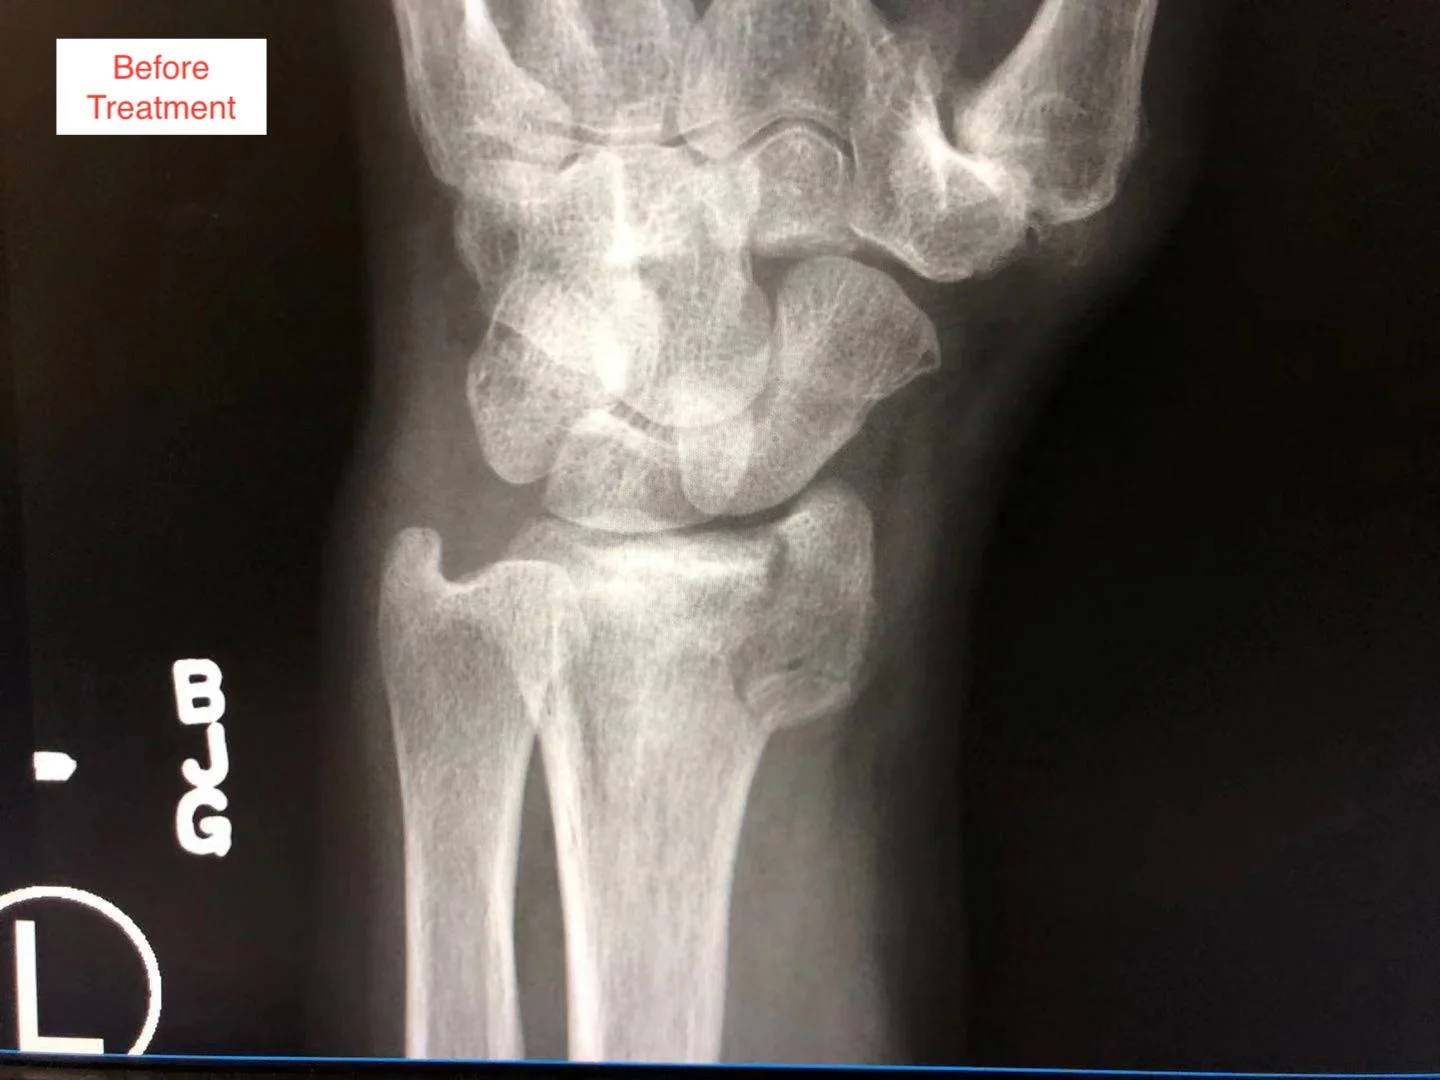

The fracture is Anti Coriolis fracture of the radial bone in the patient’s fore arm.

On this page, you can see the two X-ray pictures from before the treatment, showing the Anti Coriolis fracture of the radial bone. You can also see the X-ray pictures two weeks after the treatment, showing good bone alignment, and normal epiphyseal growth, indicating the clinical healing standard is reached.